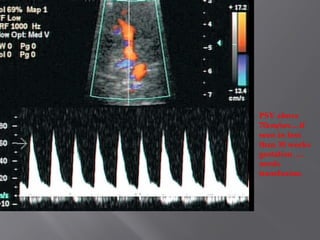

Arterial flow

Venous Flow